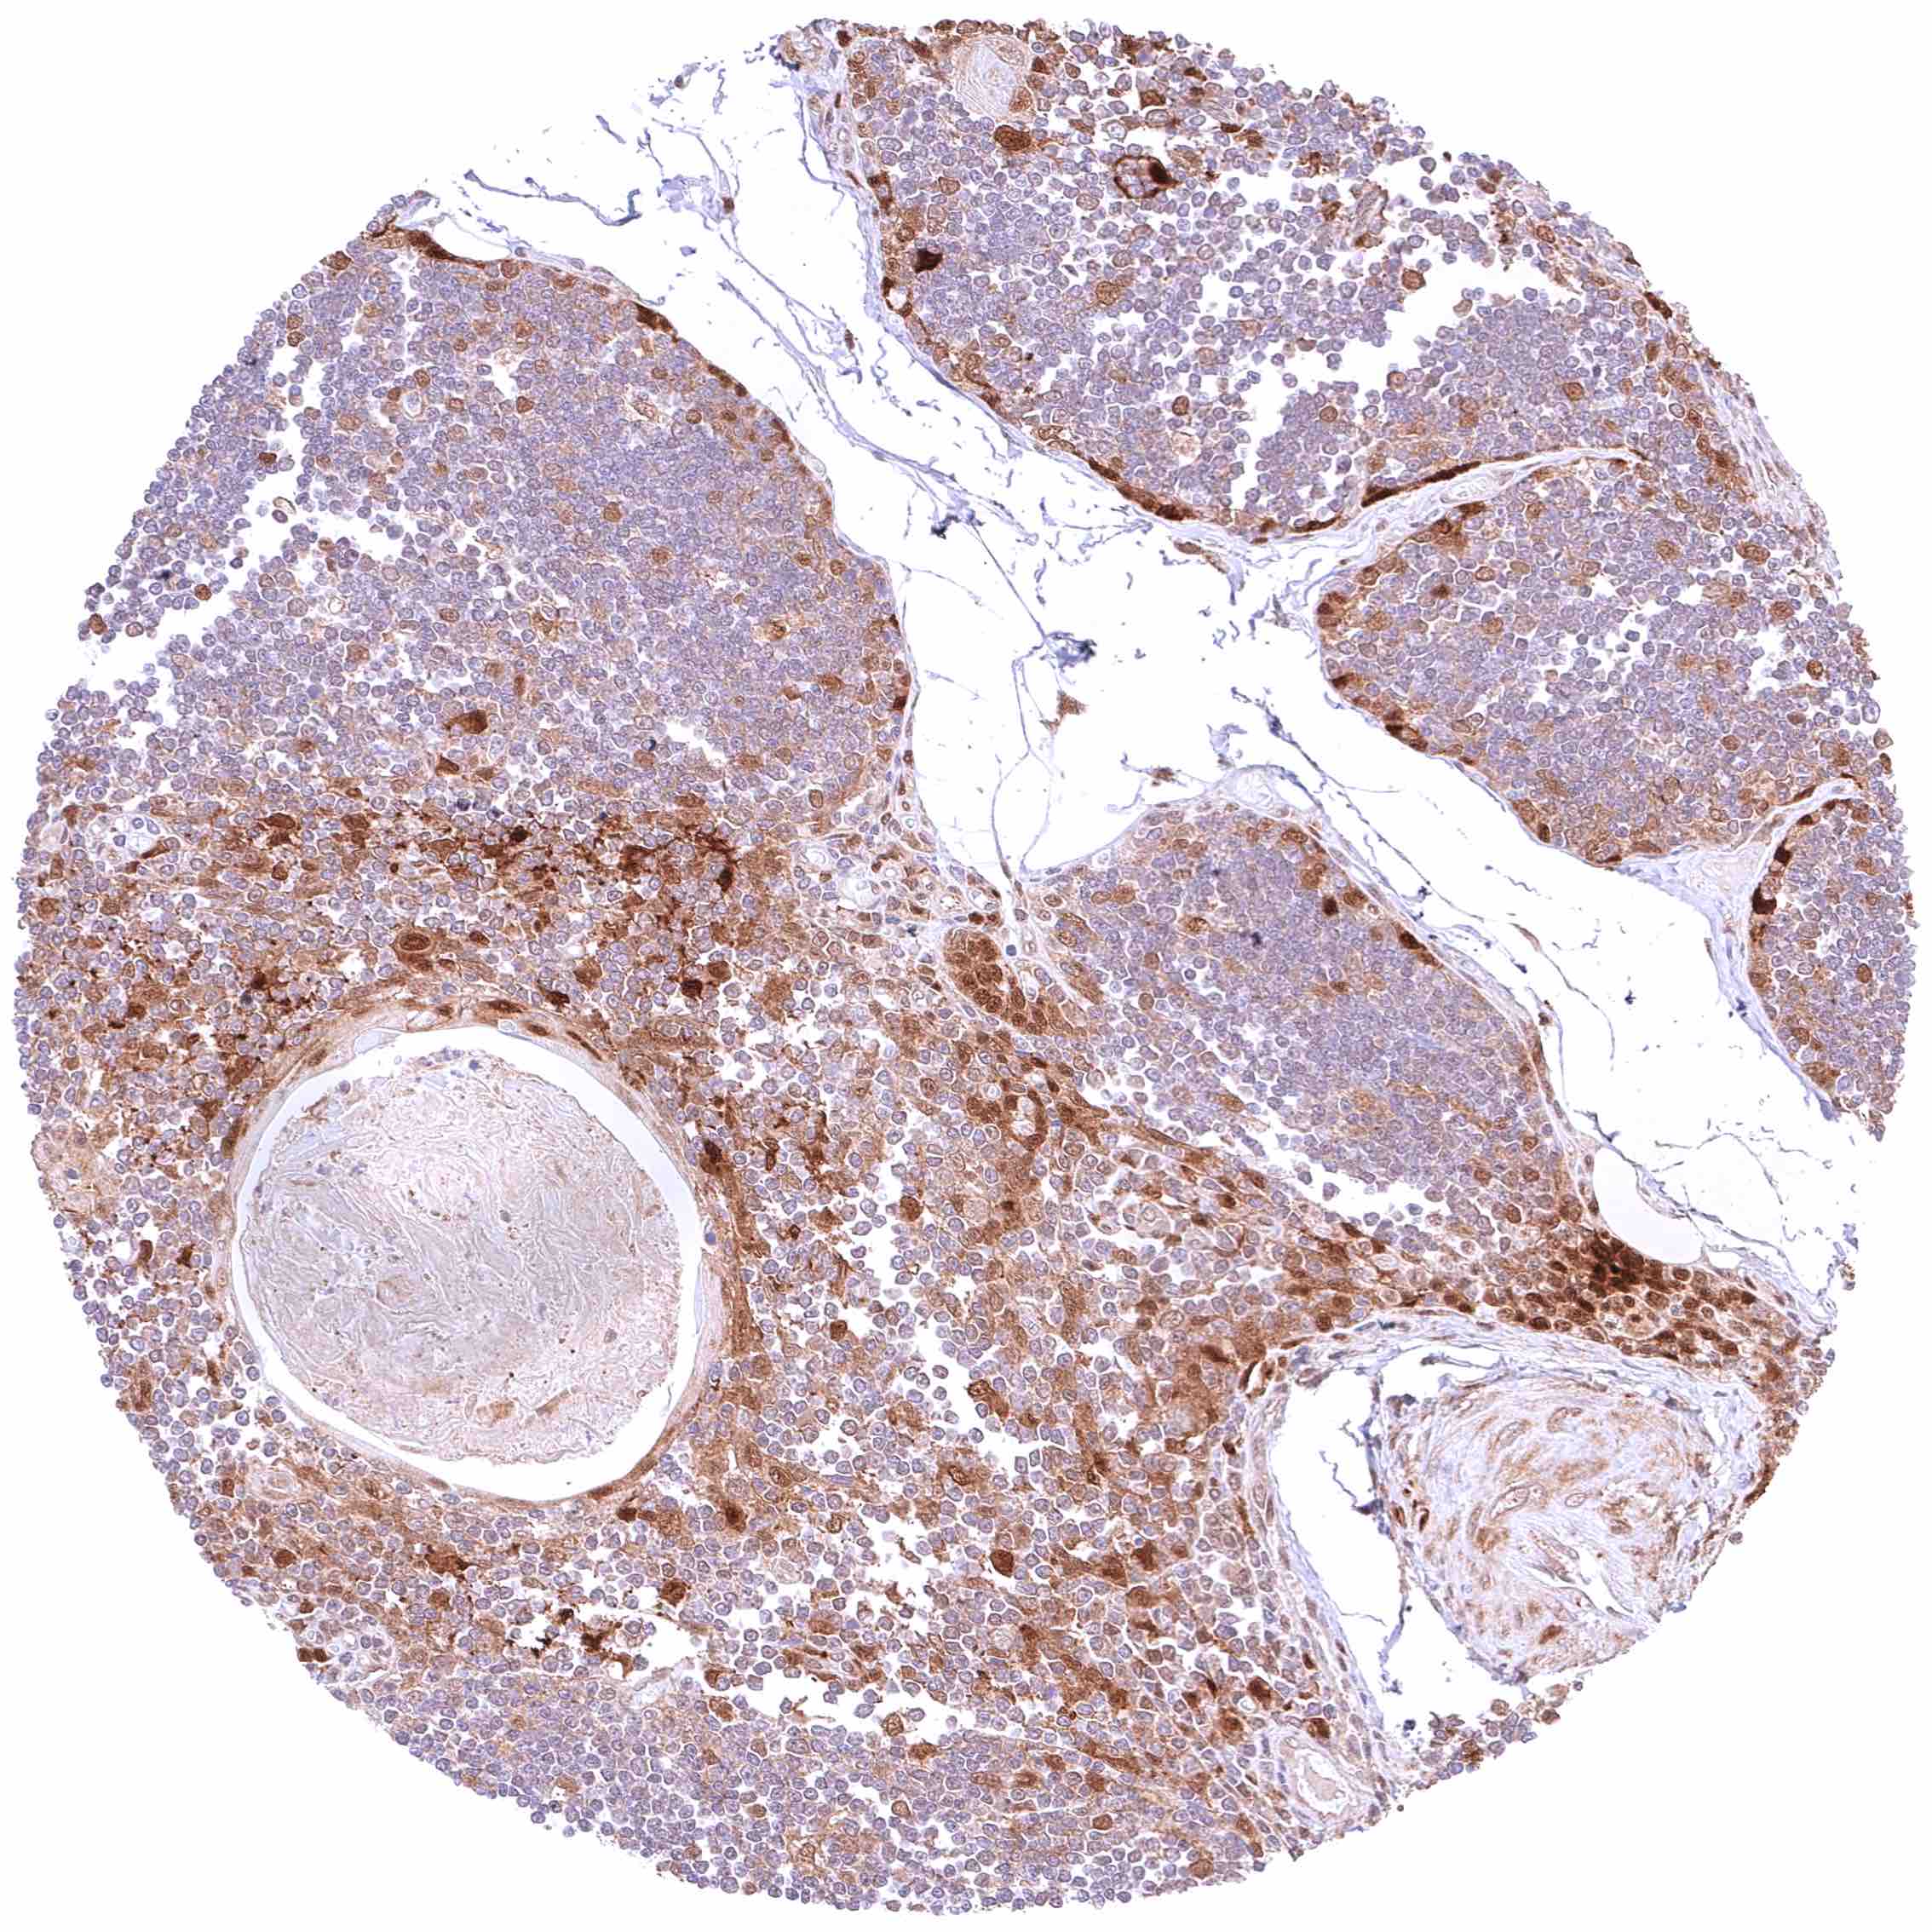

Spleen – At least a weak cytoplasmic GSTP1 positivity occurs in all cells of this sample.

Spleen – Nuclear and cytoplasmic GSTP1 positivity is limited to a small subset of cells in this sample. .jpeg